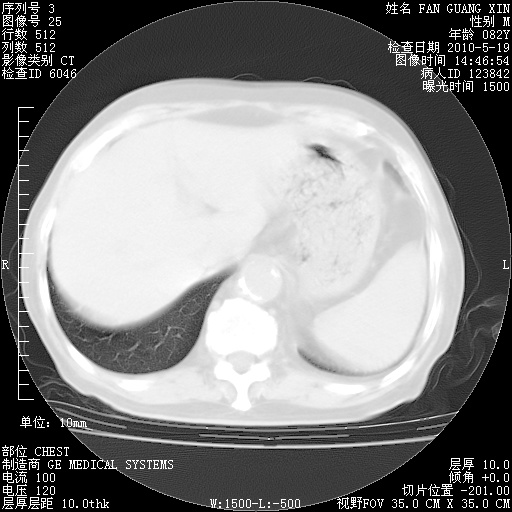

复查肺部CT,明显好转。为什么发热呢?

治疗3周后的肺部CT